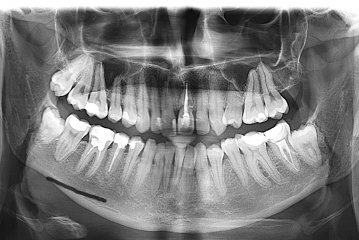

Здравствуйте! Есть ли у меня киста? Если да, то как срочно нужно делать операцию и как она называется?

Какой зуб вы имеете ввиду? Уточните. 18 и 48 зуб необходимо удалить. Далее расскажу после уточнения.